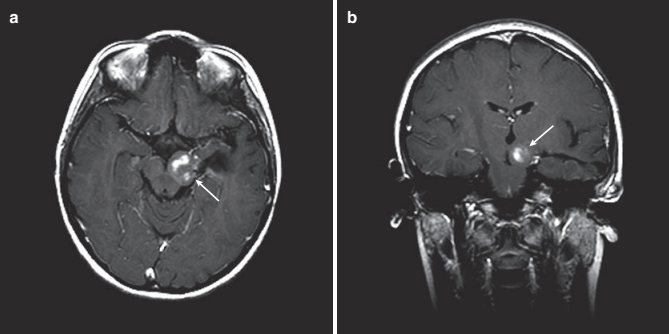

2. 诊断方法: 选择的成像方式是核磁共振。在对比剂增强后,被盖肿瘤通常均匀强化(图 4)。他们可以很大体积地占据整个被盖部,并且可因Monro孔闭塞而引起脑积水。

图4:12 岁女孩,进行性右侧肢体无力和共济失调3月。(a) 轴位T1 MRI 显示占位性病变占据脑干左侧被盖区(箭头)。(b)增强后,病灶明显均匀强化。(c) 冠状位T1 MRI增强后显示起源于左侧中脑被盖区的巨大病变,延伸到丘脑。有时,这些病灶被称为“丘脑大脑脚”病变。(d) 矢状位 T1 MRI增强后显示典型的局灶性中脑胶质瘤,中心强化。